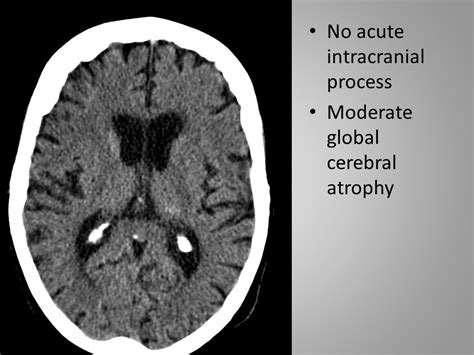

what does no intracranial process mean